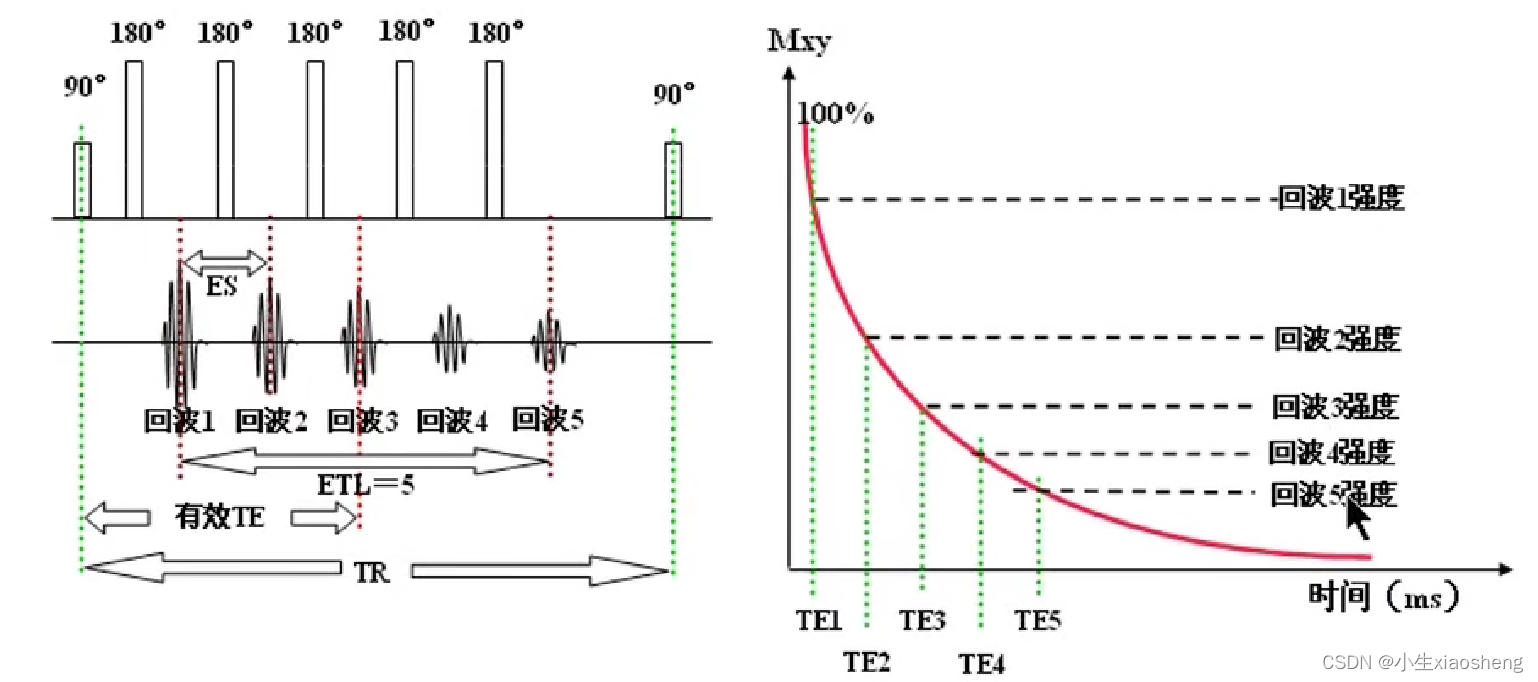

因为这里有很多的180度,所以一次能填充很多K空间线。两个90度之间的时间还是叫做TR,180度的个数叫做ETL,90度到中间个数的180度叫做有效TE,两个180度之间的叫做ES。